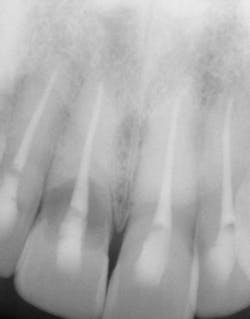

Figure 3: Tooth No. 8 shattered as expected during extraction.

Extractions are a horrifying concept, yet in actuality there is pressure but no pain. Tooth No. 8, as predicted, shattered with the first touch (see Figure 3). The sound was terrible, a super loud snap. It took a moment for me to regroup, take a breath, and literally grieve the loss of my front tooth. It sounds ridiculous, but for me this was my true moment of loss, and then beginning. The prosthodontist decided that we would prepare each tooth individually, from start to finish. One tooth out, lots of drilling to remove the root, then synthetic bone-graft material mixed with my own bone (see Figure 4). As it happens, I was offered bovine bone, treated cow bone. As a nonmeat eater, there was not a chance I could handle that in addition to losing my two front teeth! Choosing synthetic was a personal option for me. Let your patients know there are cow, pig, cadaver, and synthetic materials available; it is a personal choice (see Figure 5).